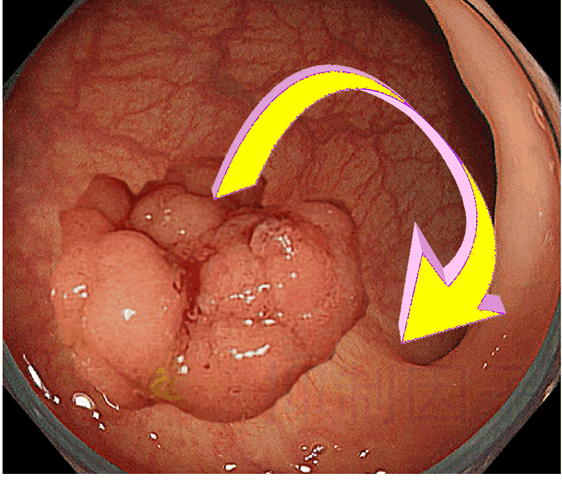

腺腫は周辺組織の大腸癌発生を予防する!

この現象はAPC変異腫瘍(腺腫に相当)で報告され(1.2)、さらにKRAS、PI3K異常腫瘍(過形成ポリープ・過誤腫に相当)でも報告されています(3)